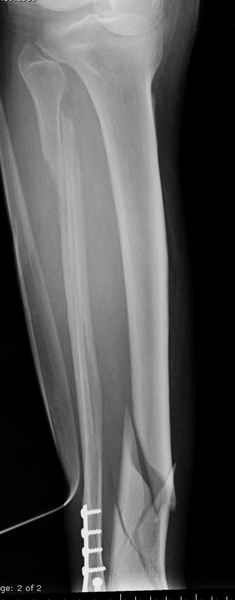

У меня молодой врач на линии, снимки отправил через эл. почту,

спрашивает что делать с больным который поступил недавно, фермер 55 лет падение при пьяной драке в баре, года два назад перенес операцию на лодыжке, на снимках и КТ перелом без вовлечения сустава,

Повреждение такой локализации, на которой применимы и аппарат (классический Илизарова или гибридный), пластина, особенно Locked Plate, и гвоздь с блокированием. В нашей клинике был бы выполнен закрытый интрамедуллярный остеосинтез. Желательно использовать гвоздь с возможностью провести более чем 2 обычных фронтальных винта в дистальном отломке.

Здесь мы использовали новый Synthes Nail с дополнительными дырками, в проксимальной части 4: по две косых и поперечные (один стандартный а другой динамический), в дистальной части две поперечные, прямая и косая. Вес больного более 120 кг, нагрузку начнем через месяц.

Получилось красиво, поздравляю. Вверху можно было ограничиться одним винтом во фронтальное статическое отверстие, зачем два 45-градусных?

При такий спирали задний край tibia может быть сломан - нет ли этого в данном случае? На всякий случай можно было ввести 1-2 винта 4,5 мм спереди назад мимо гвоздя. Хотя самый дистальный блокирующий винт, возможно, зацепил этот отломок. А какой тут диаметр гвоздя и locking винтов?